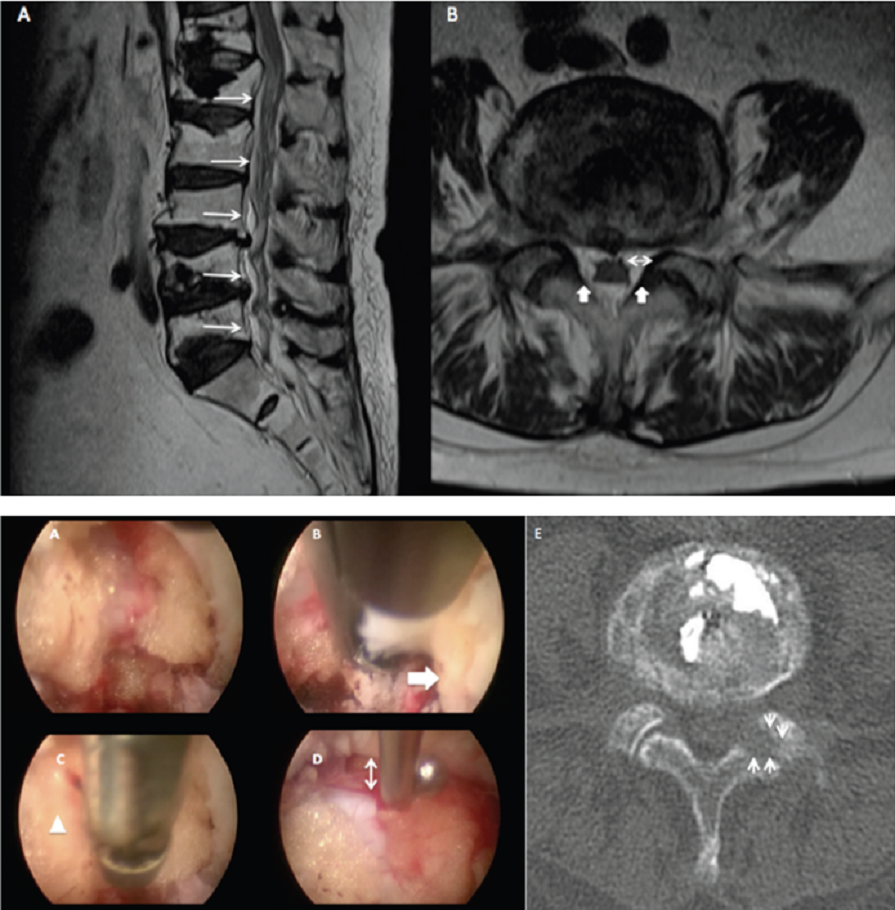

Open AccessCase Report

Endoscopic Foraminotomy in Spinal Epidural Lipomatosis, Case Report

Diego Quillo-Olvera, Jin Sung Kim, Javier Quillo-Olvera, Javier Quillo-Resendiz

International Journal of Innovative Research in Medical Science·June 30, 2019